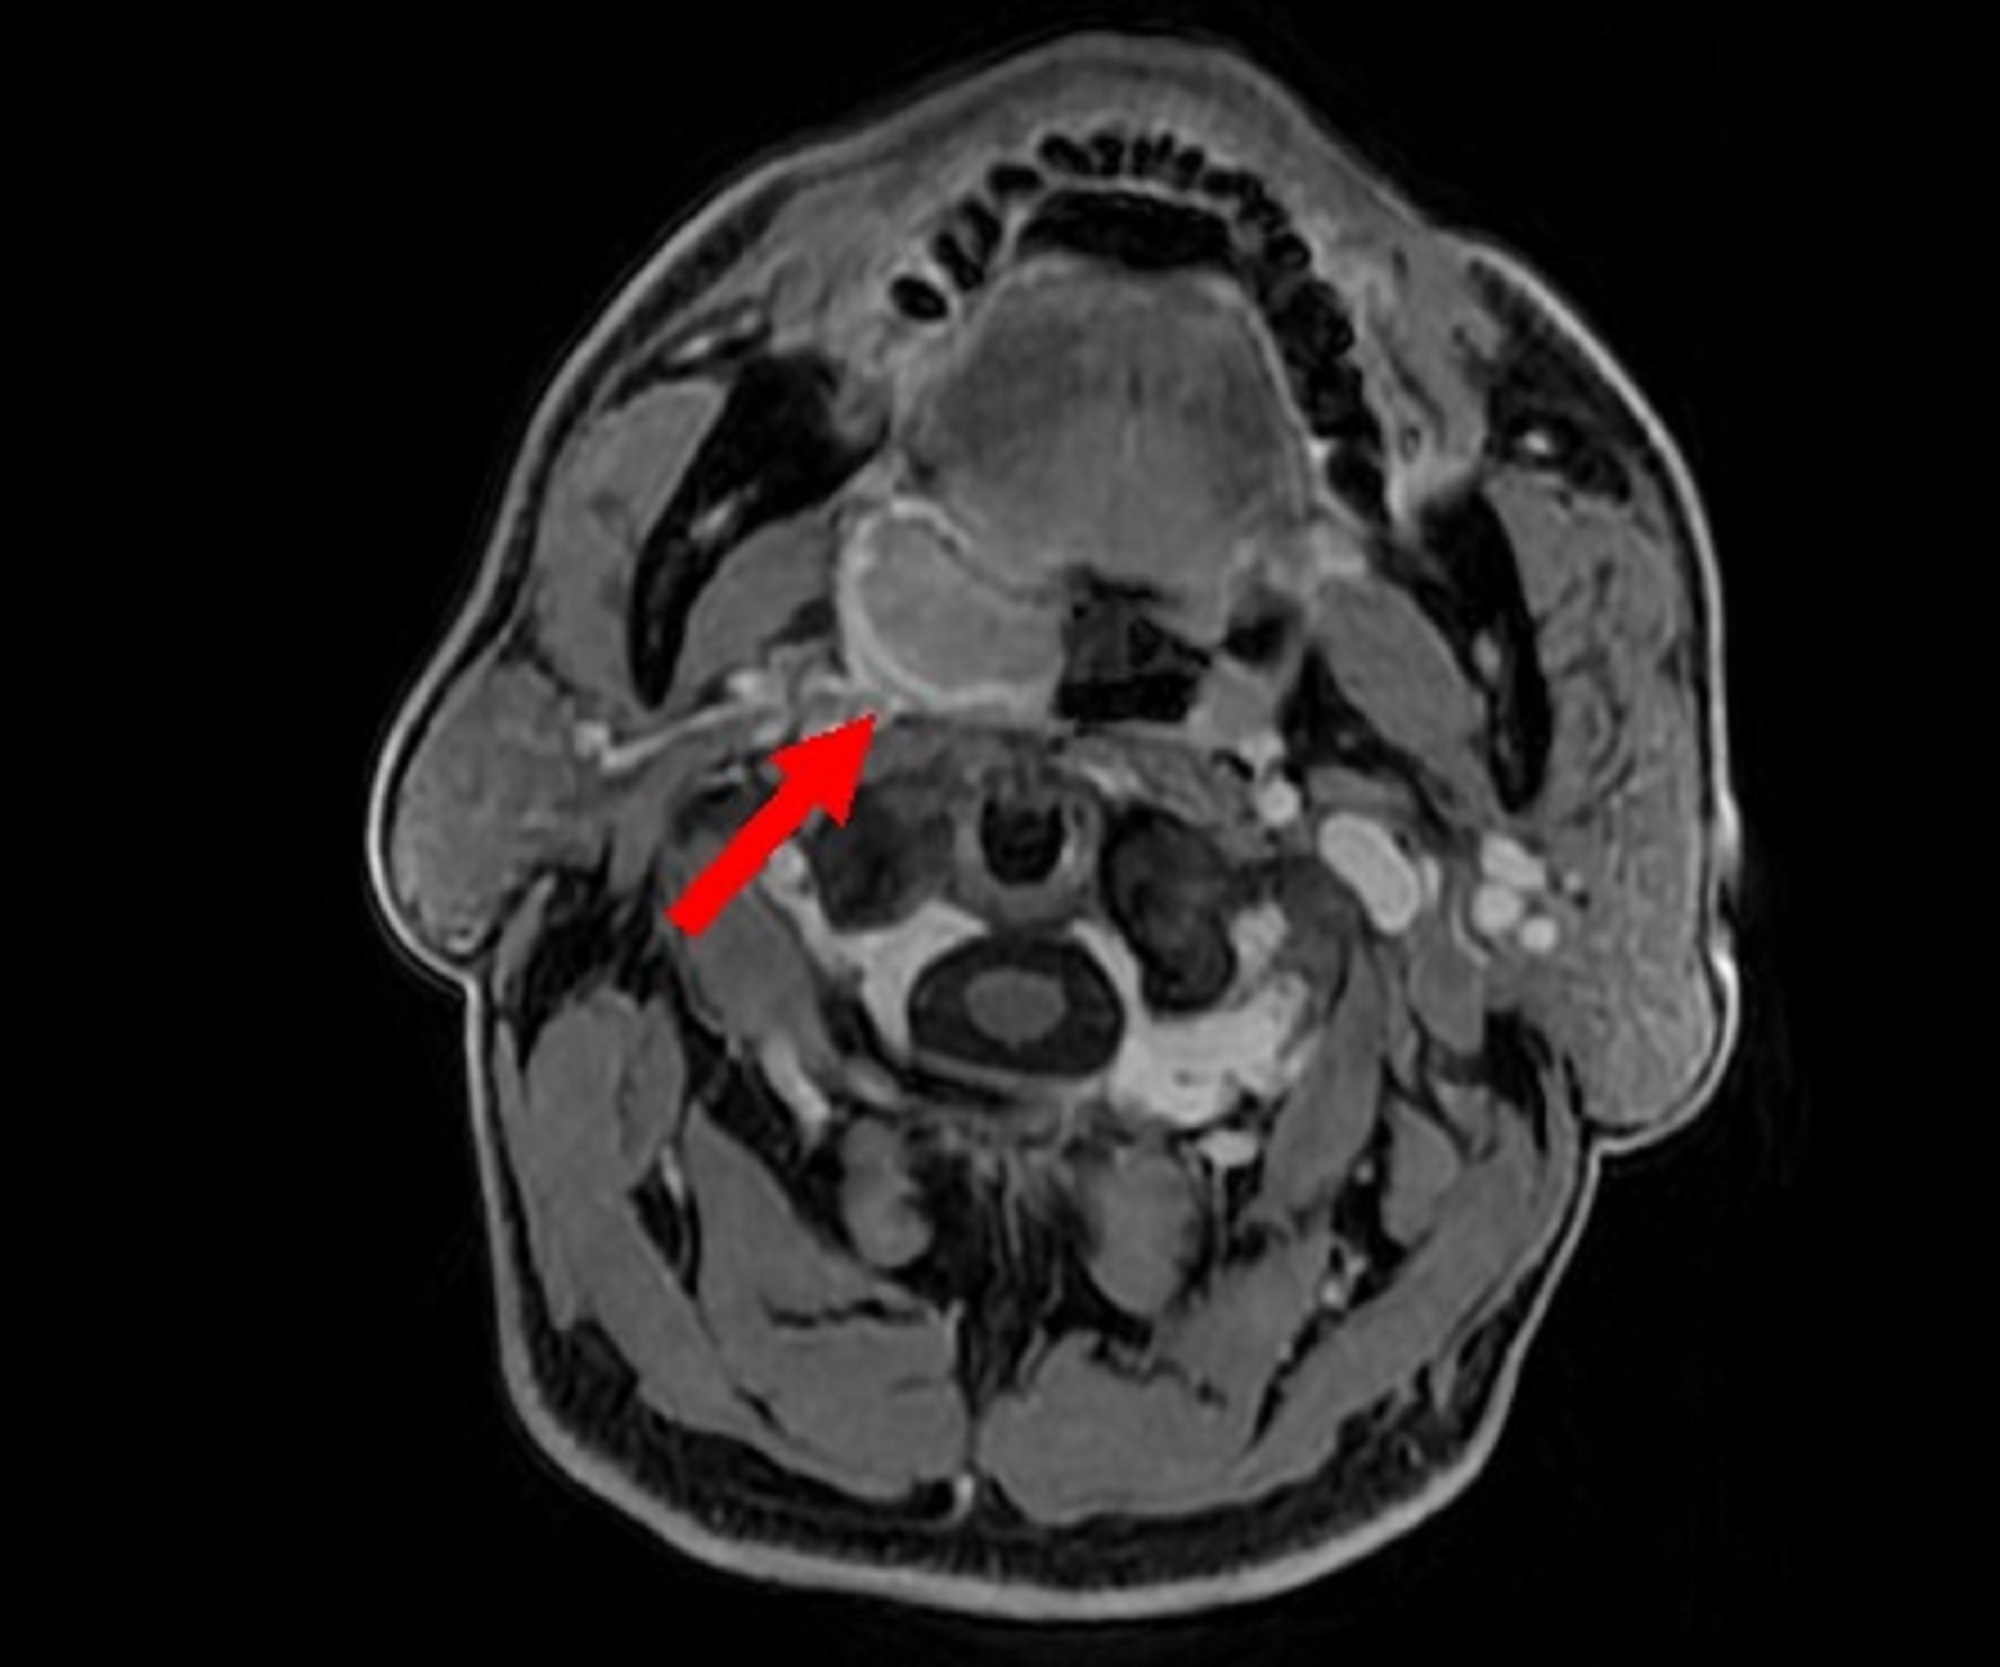

新竹臺大分院耳鼻喉部團隊近日成功運用「達文西機器手臂手術」,為一名64歲男性病人切除因人類乳突病毒(HPV)感染所致的扁桃腺癌。該名病人因右側喉嚨出現腫塊至新竹臺大分院就醫,經耳鼻喉部張峻瑋醫師診察與切片化驗後,確診為HPV感染引起的扁桃腺癌。

由於腫瘤位置隱匿、傳統手術風險高,經醫療團隊與病人充分討論後,決定採行「經口達文西機器手臂手術」進行切除。手術順利,病理報告顯示腫瘤已完全清除,病人術後恢復良好,無需接受放射線或化學治療,目前定期門診追蹤中,無復發跡象,吞嚥與飲食功能皆已恢復,生活品質明顯改善。

張峻瑋醫師指出,臺灣頭頸癌病人數逐年增加,除了與吸菸、飲酒、嚼檳榔等風險因子有關的口腔癌、口咽癌、下咽癌與喉癌外,近年由HPV感染所引起的口咽癌,尤其是扁桃腺癌的病例明顯增加,且不少病人並無菸酒習慣。由於咽喉部位解剖結構複雜、手術視野狹窄,傳統手術難度高,術後亦可能影響發聲與吞嚥功能,因此多數病人以放射線合併化學治療為主。

「達文西機器手臂的導入,為此類病人提供新的治療契機。」張峻瑋醫師進一步說明,達文西手術系統具備高解析度3D立體影像與靈活多角度的機械手臂,可於口腔與咽喉等狹小空間中進行精密操作,經自然孔道切除腫瘤,大幅降低傷口範圍與出血風險,縮短恢復期,同時保留語言與吞嚥功能,術後生活品質更佳。